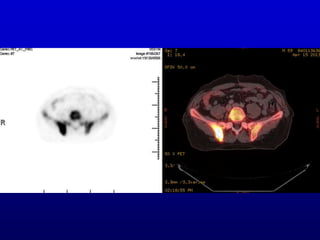

PET scan of brain in epilepsy

PET scan ofbrain in epilepsy

• 9.

We can thinkin terms of 2 interfaces between nuclear medicine and brain science (psychology, psychiatry, neuroscience, etc.): 1. Nuclear medicine (and other brain imaging modalities like MRI) can be of use in studying the brain (like the epilepsy example). 2. Brain science (e.g. psychology) can contribute to our understanding of how we perceive nuclear medicine images. This talk will emphasize the second point.

• #9 We’ll come back to the 3D bone scan. For the moment, on the theme of the interface of medical imaging and brain science, here is a nuclear medicine image of the brain in a patient with epilepsy, also a MIP. If you were fortunate enough to attend the last talk, about epilepsy, this is relevant to that. This type of study helps in planning surgery for epilepsy.